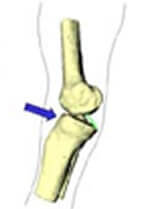

Entorse du genou par varus forcé

Un dessin est plus explicite... Choc sur l'intérieur du genou qui entraîne un varus forcé.

Ce mécanisme entraîne des lésions du ligament externe et du ligament croisé antérieur.